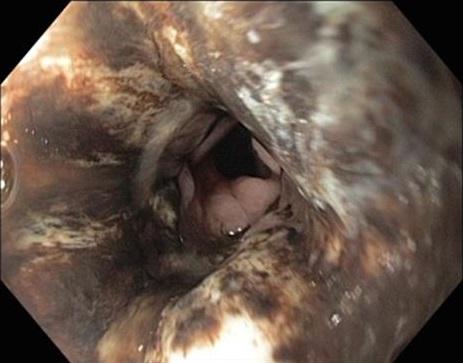

168 deelnemers

Een 85-jarige man komt naar de SEH vanwege toenemende pijn in epigastrio. Vlak ervoor heeft hij een zwarte vloeistof gebraakt. Daarnaast heeft hij melena gehad. Zijn voorgeschiedenis vermeldt hartfalen (door gedilateerde cardiomyopathie) en mitralisklepinsufficiëntie. Hij is nu hypotensief. Zijn Hb-waarde is 2,7 mmol/l, de ontstekingswaarden zijn hoog en er is sprake van acute nierinsufficiëntie. Oesofagoscopie toont dit beeld; de maag is niet aangedaan.

Wat is uw diagnose?